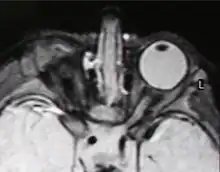

Right-sided anophthalmia (MR image) | |

MRI/CT

MRIs and CTs can be used to scan the brain and orbits. Radiologists use this to assess the internal structures of the globe, the optic nerve and extraocular muscles, and brain anatomy.